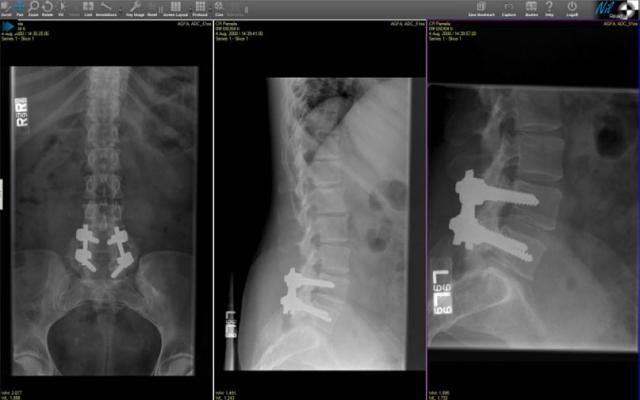

December 12, 2013 — The American College of Radiology (ACR) selected Claron’s NilRead zero-footprint diagnostic viewer for the communication of images and related data to support several new research and educational programs.  Newly FDA-cleared Claron NilRead enables fast viewing of a full range of DICOM and non-DICOM modalities in diagnostic quality with no software download or detrimental impact on performance.

Tilkin noted that the ACR will use Nil to provide remote access to images for several new projects, including teaching files for participants in some of its continuing medical education (CME) courses and in support of some of ACR’s clinical research activities. The Nil system has been integrated into several of the ACR’s workflow systems, allowing authorized users of those systems to access streamed data via web browsers and other remote devices. Nil offers a broad range of image manipulation tools and such advanced visualization features as thin/thick slabs, MIP, volume rendering, positron emissions tomography (PET)/computed tomography (CT) fusion and more. Powerful server-side processing reformats images immediately.